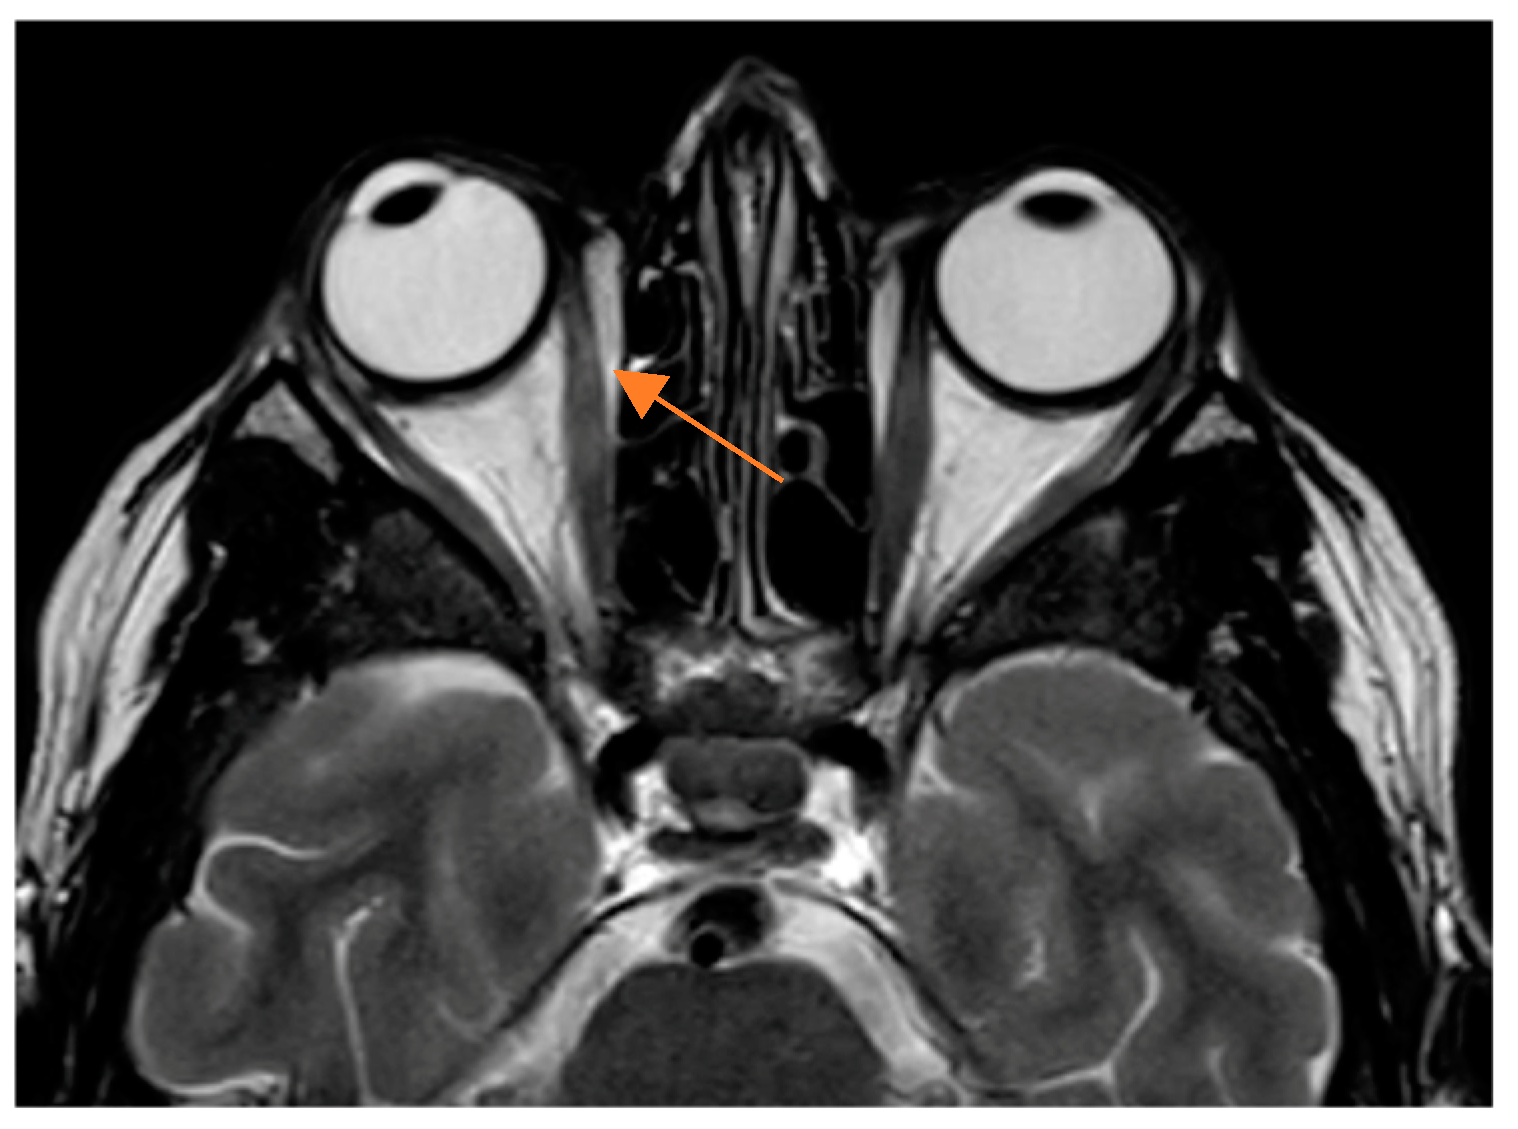

| MRI * (T2-weighted) | Hyperintense signal | Hyperintensity indicative of acute inflammation, edema, and increased fluid. |

| Gadolinium Contrast (MRI) * | Enhancement | Increased contrast enhancement indicating inflammation or venous congestion. |

| Fat-suppressed MRI (STIR) * | Enhanced signal | Clearly delineates optic nerve involvement and inflammatory changes. |